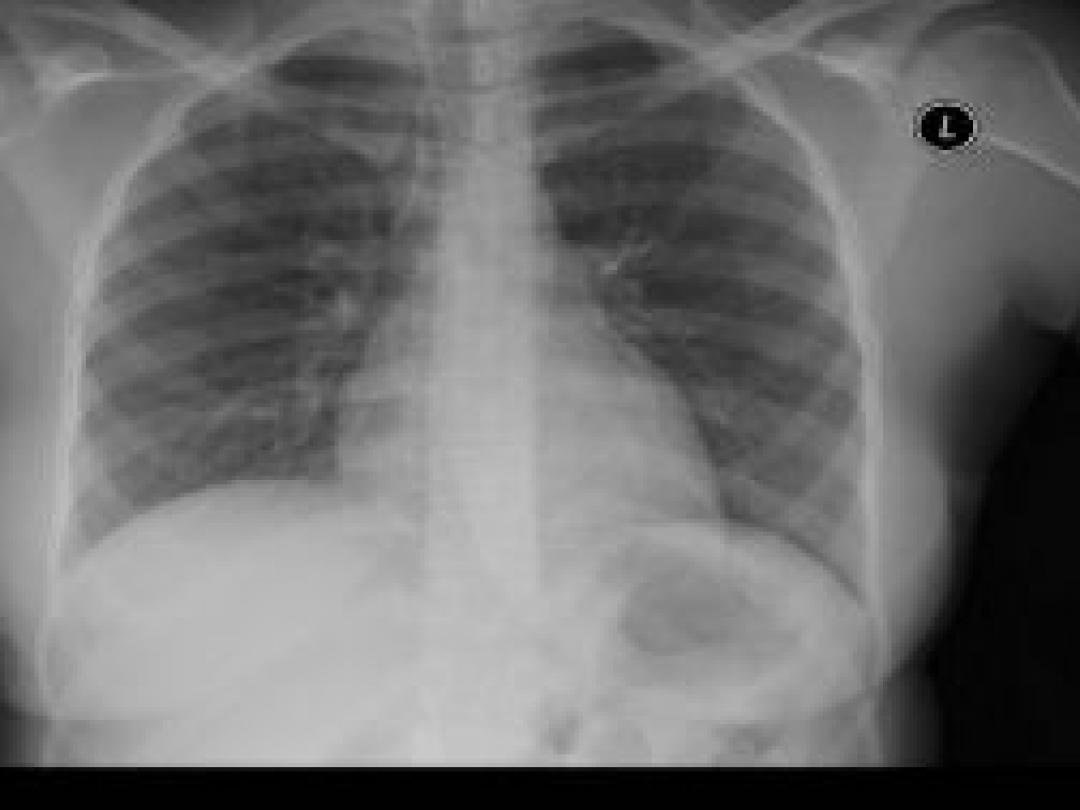

Geen longembolie, maar wat dan wel?

Als huisartsen vermoeden dat een patiënt een longembolie heeft, vinden ze vaak andere klinisch relevante aandoeningen, zoals een longontsteking. Dat schrijven Petra Erkens van het MUMC en collega's in Family Practice (2014; epub 12 september). Een positieve Wells-score (> 4) of een positieve uitslag van de D-dimeertest waren…